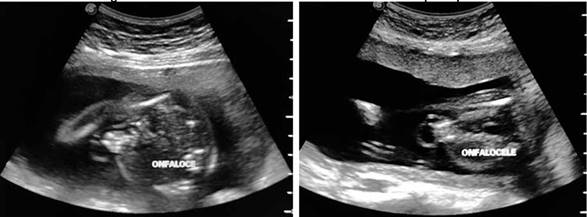

Durante su estadía se solicita una ecografía obstétrica estructural temprana, realizada por el servicio de Medicina Materno Fetal, la cual reporta un feto único vivo en presentación pélvica, situación longitudinal, dorso derecho, fetometría promedio 19.6 semanas de gestación, peso fetal estimado de 363 +/- 480 gramos, líquido amniótico cualitativamente normal con pool máximo de 4. A la evaluación estructural se observa a nivel cefálico, incremento del pliegue nucal (Figura 1), edema pericraneal y prenasal, fosa posterior aumentada y desplazada, con agenesia parcial de vermis cerebeloso. A nivel de columna cervical se encuentra edema, con tabicación que sugieren un higroma quístico. A nivel de tórax se evidencia edema de tejido subcutáneo, en el corte de cuatro cámaras se observa área anecoica en forma de luna bilateral importante que rodea al corazón, sugestivo de hidrotórax bilateral. No se aprecia tejido pulmonar en ningún hemitórax. A nivel de abdomen se evidencia defecto de pared de aproximadamente 12 mm en su base, por donde protruyen asas intestinales con membrana que los recubre, siendo los diámetros del saco del defecto de 25 x 20 mm (Figura 2). Todos los datos fueron compatibles con un embarazo de 19.4 semanas (según ecografía obstétrica temprana) y feto con Hidrops fetal no inmune con higroma quístico.

FIGURA 1. Imagen hipoecogénica compatible con acumulación de líquido a nivel subcutáneo.

FIGURA 2. Imagen de exteriorización de contenido abdominal, recubierta por tejido membranoso.